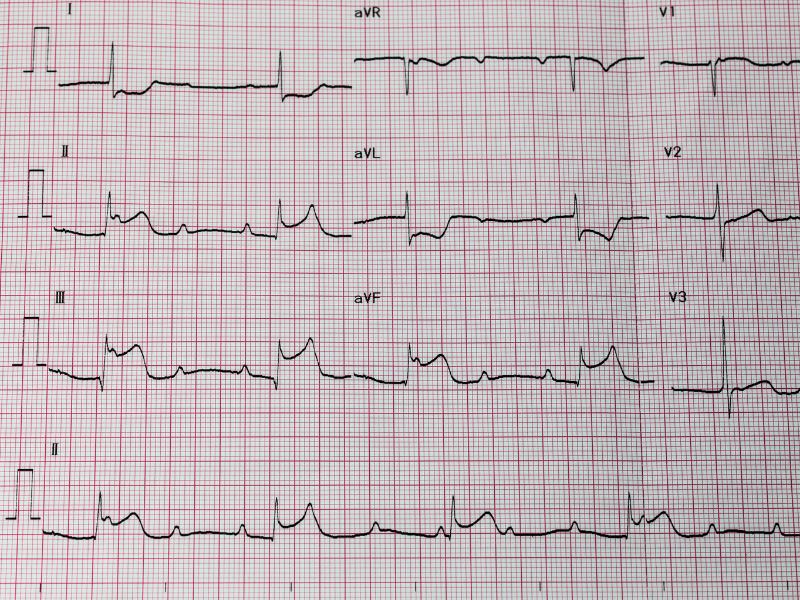

O ECG também pode nortear o tratamento clínico?

A última etapa no processo de extrair o máximo de informações do ECG do nosso paciente é entender como os achados podem nortear o tratamento do paciente, seja no curto prazo, seja no longo prazo.

Um exemplo bem importante na prática clínica de qualquer médico plantonista de PS é saber identificar a artéria culpada para lesão aguda do miocárdio durante um infarto. Quando você identifica, por exemplo, que o supra de ST está presente nas derivações DII, DIII e aVF, você está delimitando um território que é a parede inferior do ventrículo esquerdo e também levantando suspeitas de acometimento de infarto de ventrículo direito (VD), que poderia ser confirmado pela presença de alterações nas derivações direitas V3R e V4R.

Figura 9: IAM de parede inferior. Considerar infarto de VD e providenciar ECG com derivações direitas V3R e V4R.

Figura 9: IAM de parede inferior. Considerar infarto de VD e providenciar ECG com derivações direitas V3R e V4R.

Confirmado que o ventrículo direito foi acometido, você precisará direcionar o seu tratamento para as possíveis repercussões previstas nos casos de infarto de VD. Ou seja, essa informação, extraída do ECG, vai te permitir considerar a reposição volêmica como parte inicial do atendimento para manter o débito do ventrículo direito. Além disso, o ECG também está orientando que a artéria culpada é a coronária direita e essa informação vai nortear a abordagem da equipe da hemodinâmica durante o procedimento de angioplastia primária, ainda que o paciente tenha outras lesões críticas observadas à angiografia.

Caso a opção para o atendimento desse paciente fosse trombólise, o ECG também seria um dos critérios importantes para acompanharmos de forma seriada, pois a diminuição progressiva do supra de ST seria um importante indicativo de que o tratamento instituído está dando certo.

Figura 8: Sempre faça o ECG de controle após a reversão de uma taquicardia supraventricular paroxística. Figura 9: IAM de parede inferior. Considerar infarto de VD e providenciar ECG com derivações direitas V3R e V4R.

Figura 9: IAM de parede inferior. Considerar infarto de VD e providenciar ECG com derivações direitas V3R e V4R.